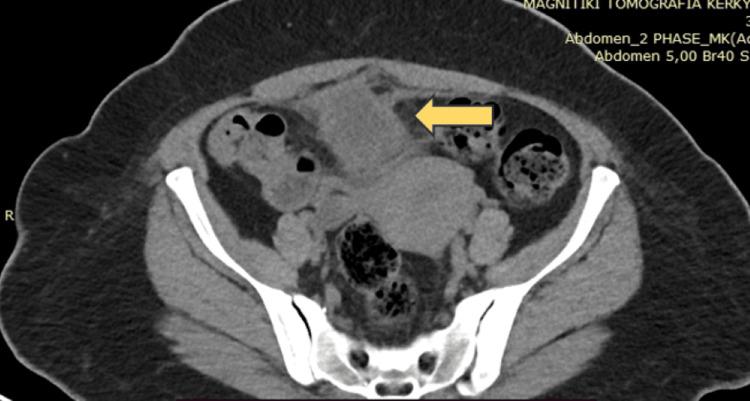

Urachal cancer is a rare and aggressive type of cancer, frequently characterized by a lack of prominent symptoms. We herein report a case of a 50-year-old female with mucin-producing adenocarcinoma originating from the urachus who underwent partial cystectomy and the patient remains disease-free for 30 months after treatment.

脐尿管癌是一种罕见且侵袭性强的癌症,通常表现为缺乏明显症状。我们在此报告一例50岁女性,患有起源于脐尿管的黏液腺癌,接受了部分膀胱切除术,治疗后患者已无病生存30个月。